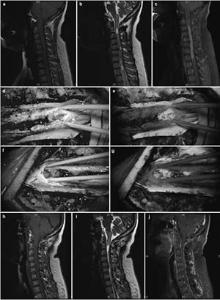

20171023161526 Figure 1 Pre- and postoperative magnetic resonance imaging of intramedullary ependymomas at C1–T1, and intraoperative observations. (a) Preoperative sagittal T1 image reveals spinal cord thickening. (b) T2 image shows high intramedullary signal intensity at C1–T1, but no signal at either end. (c) Enhanced scanning reveals distinctive tumor enhancement. (d) Intact tumor with clear boundaries, as viewed under a microscope. (e) Tumor images, viewed via fluorescence microscopy, showing a distinctive basal structure. Sagittal T1 (f) and T2 (g) images, 3 months after surgery, do not show tumor residuals or relapses.

20171023161638 Figure 2 Pre- and postoperative magnetic resonance imaging of intramedullary ependymomas at C2–T2, and intraoperative observations. (a) Preoperative sagittal T1 image reveals spinal cord thickening. (b) T2 image shows high intramedullary signal intensity at C2–T2, but no signal at either end. (c) Enhanced scanning reveals distinctive enhancement of the tumor mass and cyst wall. Tumor ends, as micrographed using white light (d) and fluorescence (e). (f) Cysts at the tumor ends, microscopically probed with white light, do not show the tumor. (g) Distinct cyst walls are evident under fluorescent illumination, revealing a suspicious tumor that was removed. At 3 months, the sagittal T1 (h) and T2 (i) images and the enhanced scan (j) reveal no evidence of tumor residuals or relapses.